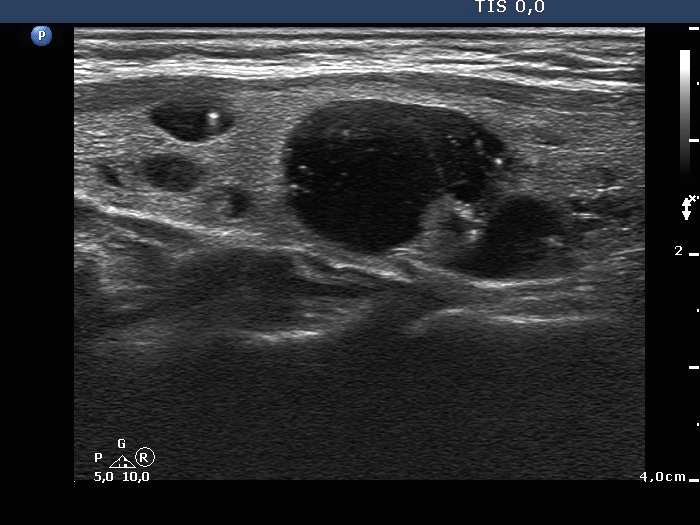

The composition of the nodule - case 142 (ultrasonographic picture 4)

Right lobe, another longitudinal scan. The cystic nodule has a dorsal echonormal solid part. Therefore, this lesion seems to be a peripheral-type cystic nodule in this section.